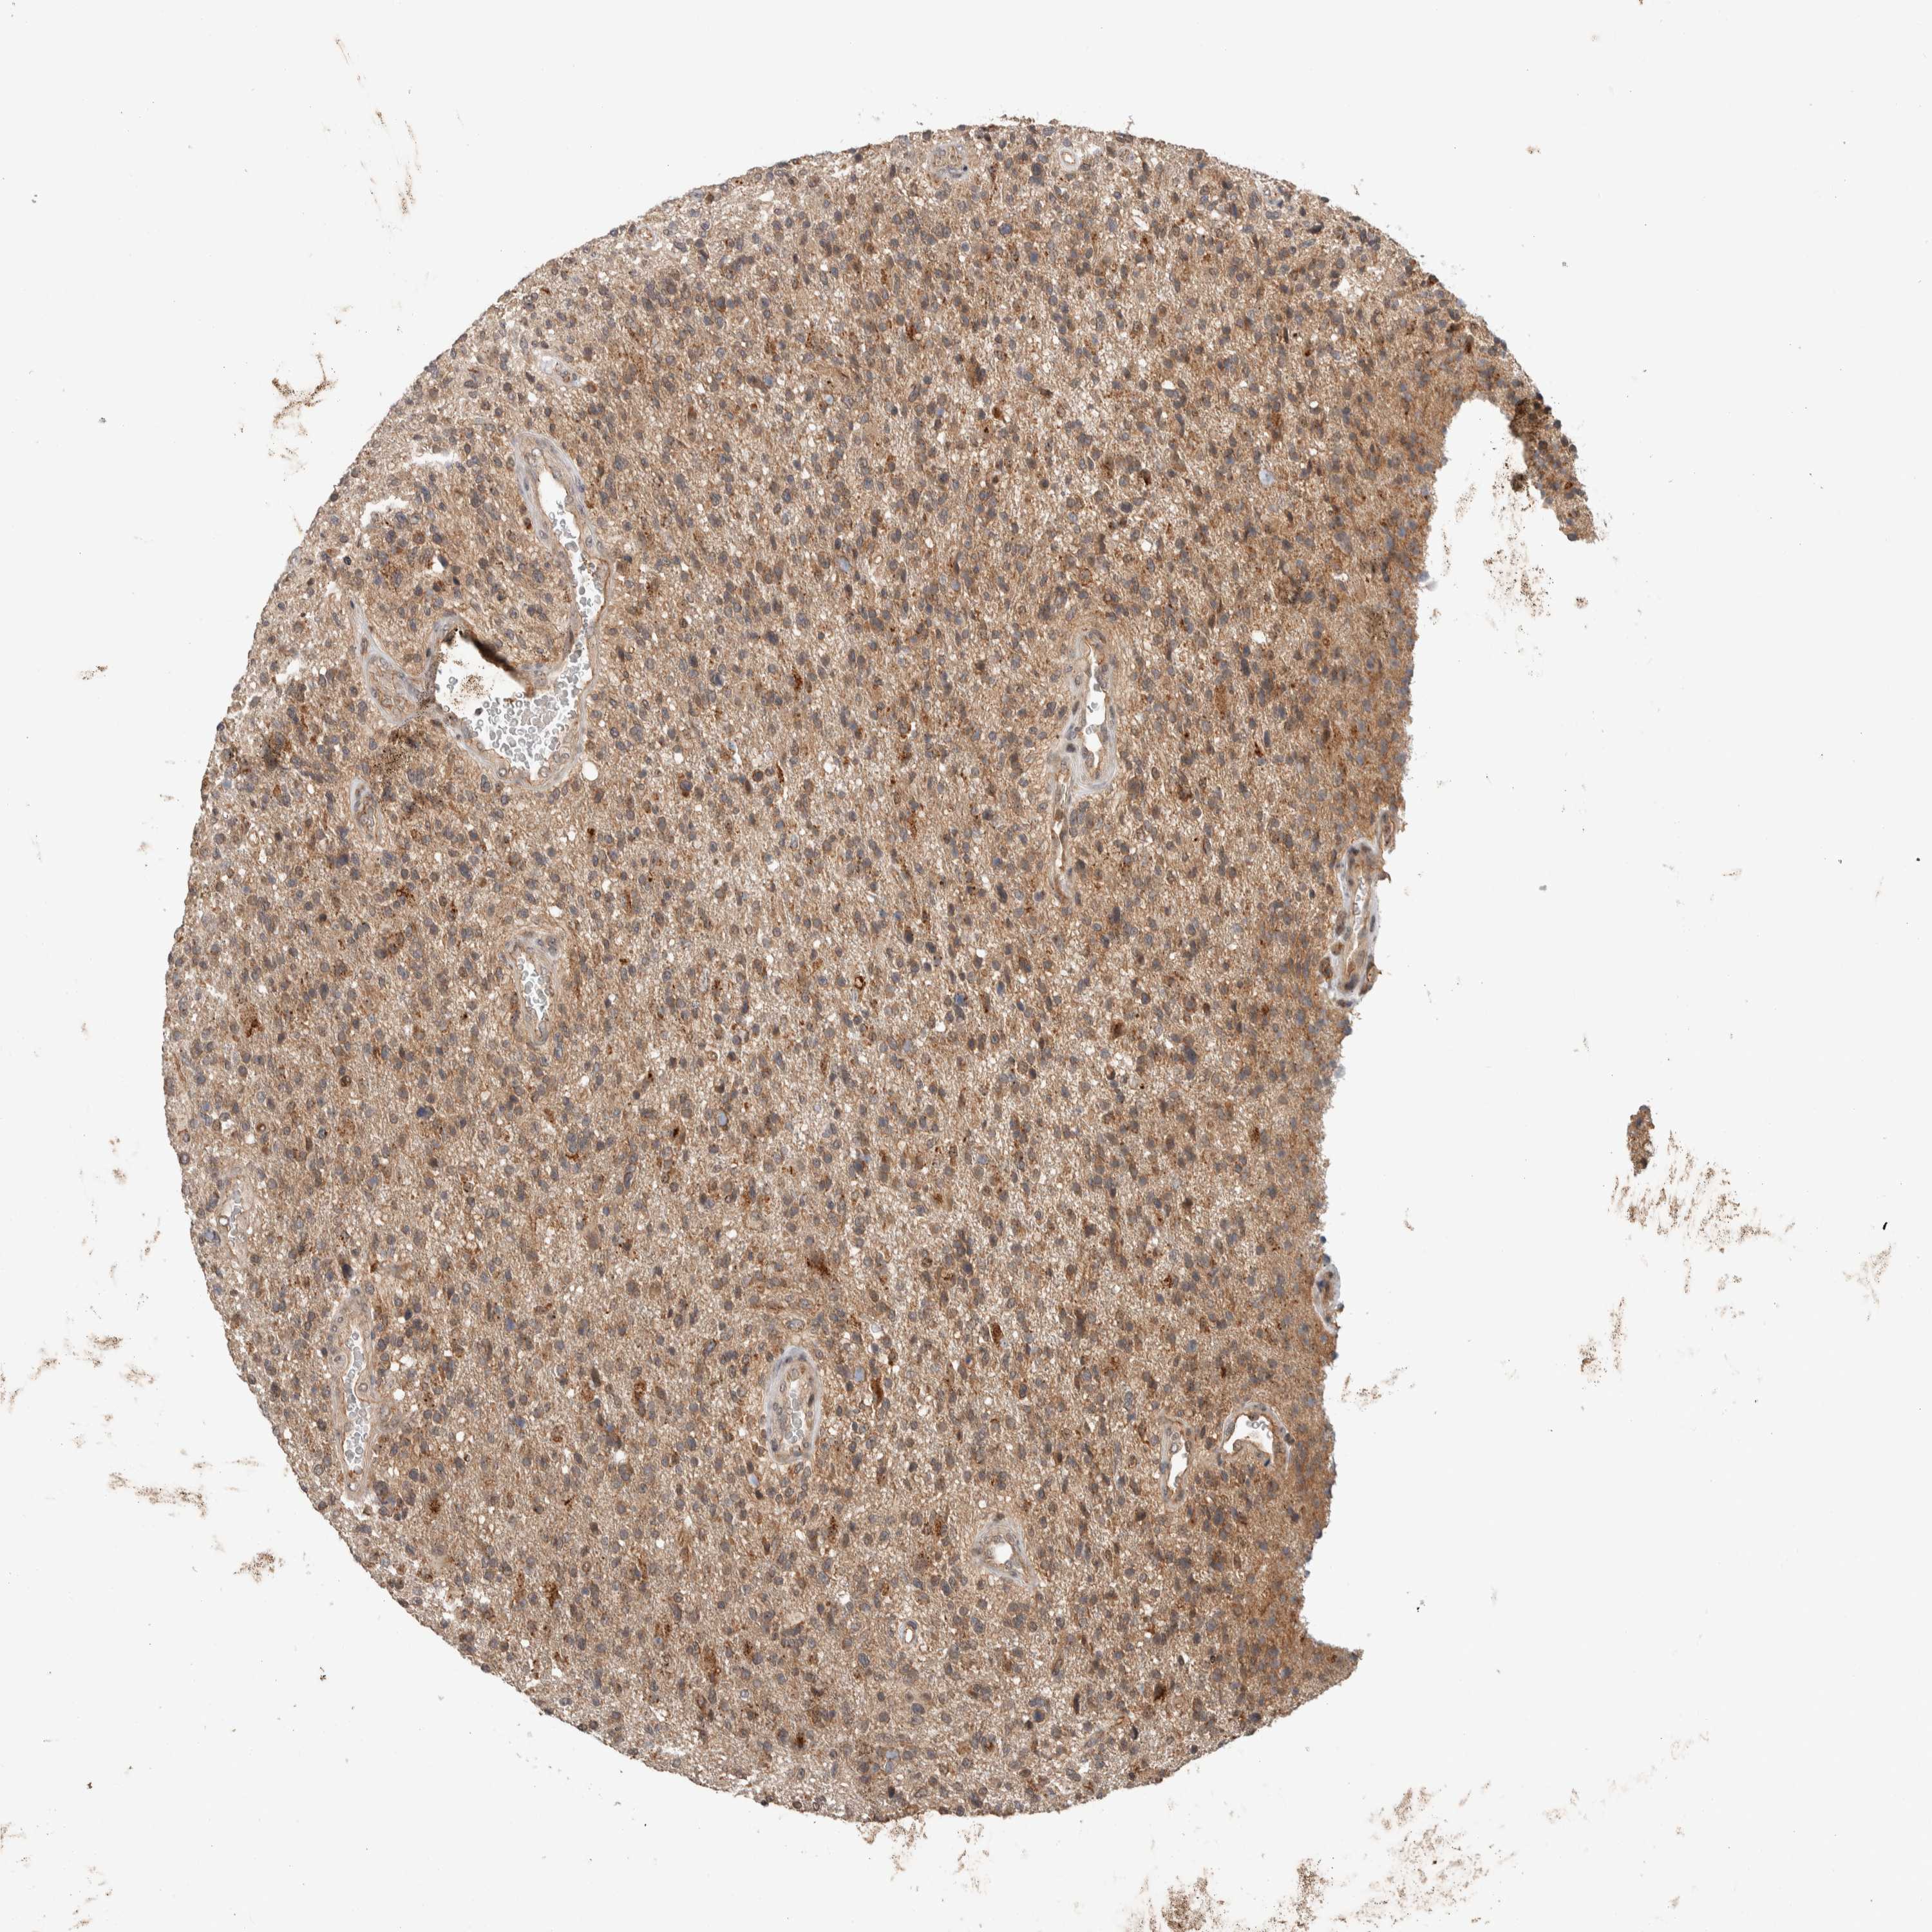

GLIOMA - Protein expressioni

A mouse-over function shows sample information and annotation data. Click on an image to view it in a full screen mode. Samples can be filtered based on level of antibody staining by selecting one or several of the following categories: high, medium, low and not detected. The assay and annotation is described here.

Note that samples used for immunohistochemistry by the Human Protein Atlas do not correspond to samples in the TCGA dataset.

Antibody stainingi

Antibody staining in the annotated cell types in the current human tissue is reported as not detected, low, medium, or high, based on conventional immunohistochemistry profiling in selected tissues. This score is based on the combination of the staining intensity and fraction of stained cells.

Each image is clickable and will lead to virtual microscopy that enables deeper exploration of all samples and also displays staining intensity scores, fraction scores and subcellular localization as well as patient and tissue information for each sample.

Antibody HPA023938

Antibody HPA023945

Antibody HPA024011

Antibody CAB020841

Staining

High

Medium

Low

Not detected

Intensity

Strong

Moderate

Weak

Negative

Quantity

>75%

75%-25%

<25%

None

Location

Nuclear

Cytoplasmic/membranous

Cytoplasmic/membranous,nuclear

Glioma, malignant, High grade

Glioma, malignant, Low grade